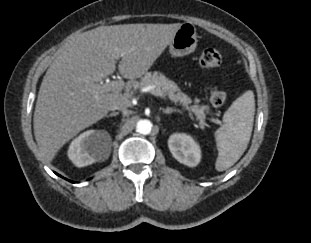

Современным высокоинформативным способом выявления патологических изменений поджелудочной железы является мультиспиральная компьютерная томография с прицельным сканированием органа. Метод КТ основан на применении рентгеновского излучения и способности органов и тканей поглощать рентгеновские лучи.

При необходимости детальной визуализации структуры железы, особенно в случае подозрения на развитие опухоли, назначается КТ поджелудочной железы с контрастом. Для этого применяются йодсодержащие контрастные препараты, которые вводятся пациенту внутривенно. Контрастное вещество, попадая в кровоток, контрастирует кровеносные сосуды и патологические очаги на фоне окружающих здоровых тканей.

Контрастирование позволяет отличить зоны воспаления, деструкции, разрастания фиброзной ткани и опухолевой трансформации от сохраненной паренхимы поджелудочной железы. КТ поджелудочной железы с контрастированием дает исчерпывающую информацию о состоянии органа и патологических процессах в нем.